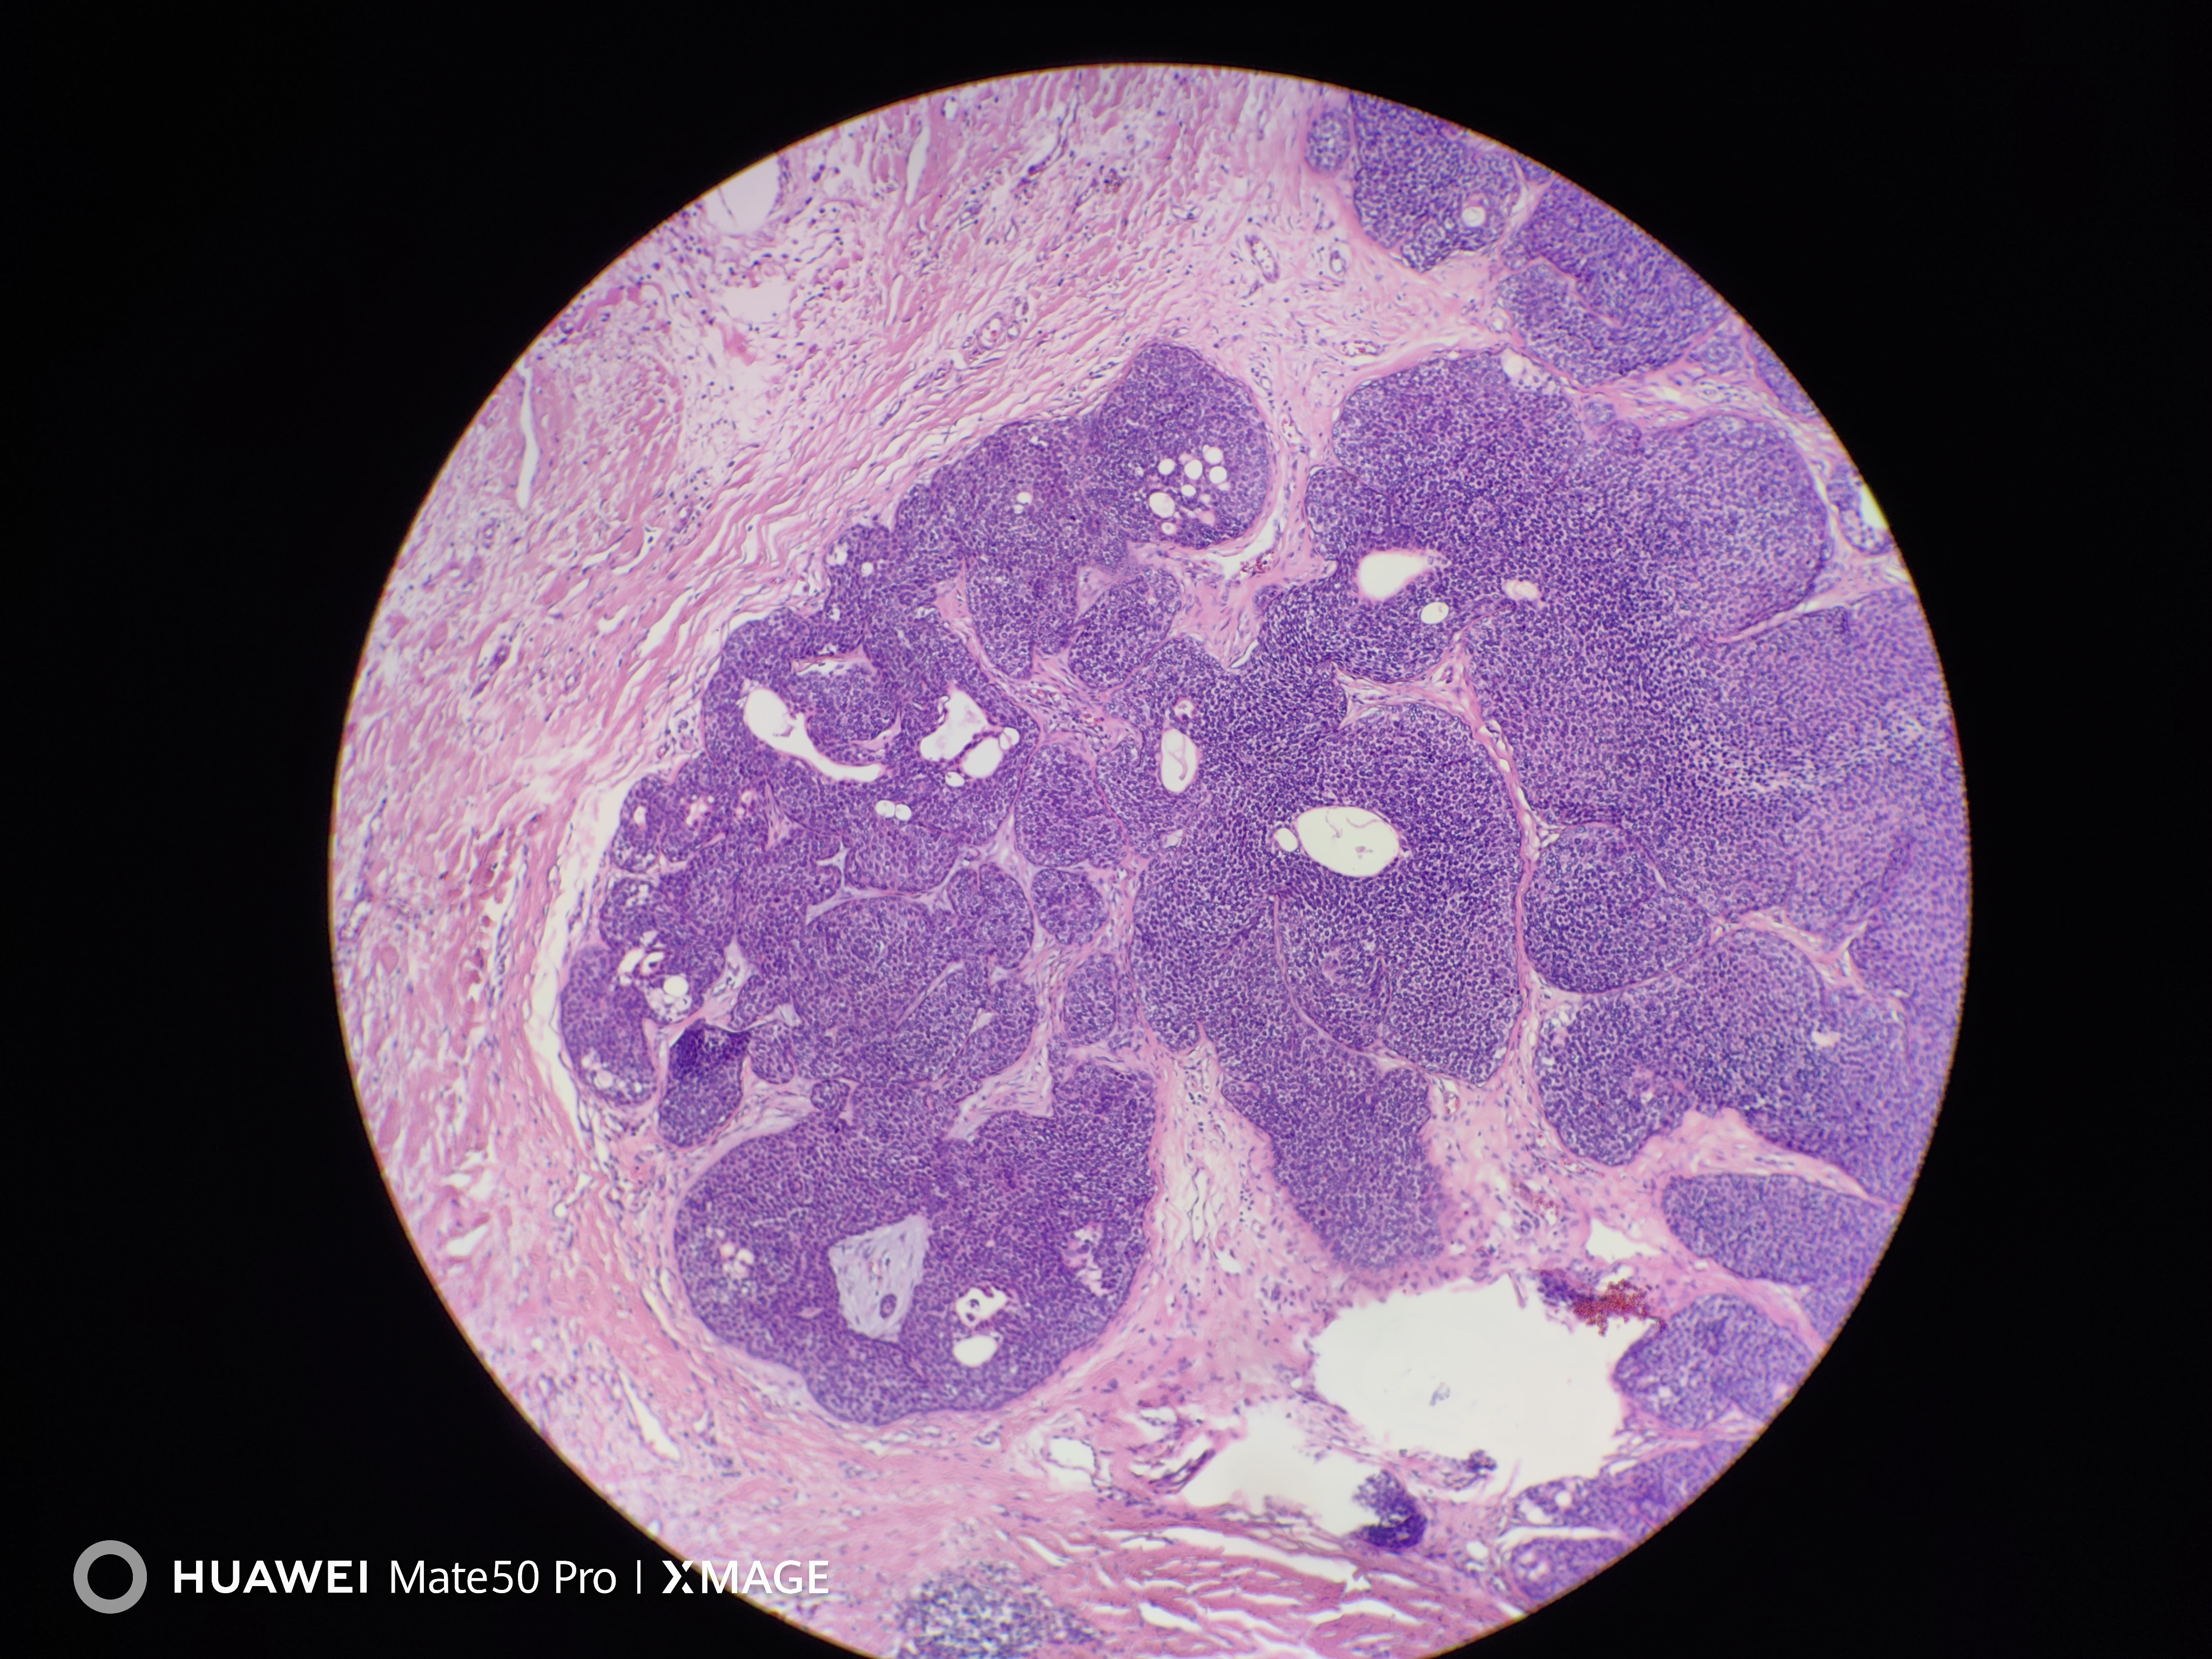

头皮肿物

头皮皮肤肿物3年余

头皮皮肤肿物

灰褐不整形组织一块,大小2.0*1.7*1.0cm,表面覆梭皮,切面灰白灰褐,实性质中。

考虑:汗孔瘤or圆柱瘤?

汗孔样汗腺瘤。

皮脂腺瘤

皮脂腺分化及导管

汗孔瘤伴皮脂腺分化。